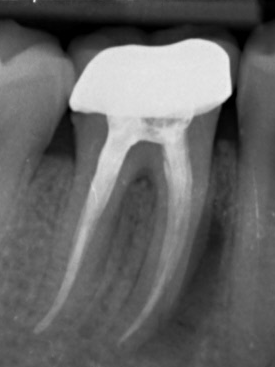

Op de foto zie je duidelijk de ontsteking. Buccaal bevindt zich een pocket/ fistel van 10 mm en linguaal bevindt zich een fistel. Op de foto lijkt het erop (zie bijlage) dat ze een breuk ziet ion het apicale 1/3 deel van de mesiale wortel.

Ik word nu doorverwezen, maar kans is zeer groot dat de kies getrokken moet worden. Daar zit ik zelf totaal niet op te wachten. Ik heb eerder een wortelbreuk gehad (ook waar wortelkanaalbehandeling is uitgevoerd). Destijds had ik echt heel veel pijn aan die wortel. Dit keer heb ik alleen irritatie van het tandvlees, maar geen pijn. Ik kan gewoon eten, drinken, het tandvlees poetsen etc.

Dit lijkt idd op een wortel fractuur. Als lokaal ( op een plek) 10mm een pocket zit zeker. Een hemisectie (verwijdering v voorste wortel) lijkt, indien goed uitgevoerd, een prima oplossing. Anders hele kies verwijderen en een implantaat ( omdat buur elementen op deze foto niet gevuld lijken) of als meerdere kiezen afwezig zijn een frame prothese Anders daar ook implantaten of ander vaste constructie afhankelijk v wat u er voor over heeft/kunt uitgeven.